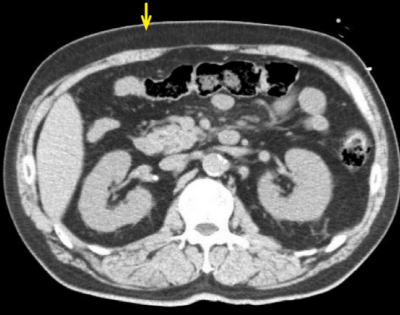

腹部CTを別に示す。矢印で示す部位について正しいのはどれか。

皮下脂肪だよ。

a 脂肪細胞で構成される。肥満細胞(マスト細胞)は免疫に関与する細胞。紛らわしい名。

b BMIは体重と身長から算出。

c 正解(*´ω`*) - 皮下脂肪型肥満は洋梨、内臓脂肪型はりんごと呼ばれる。

d メタボは内臓脂肪が多い場合です。